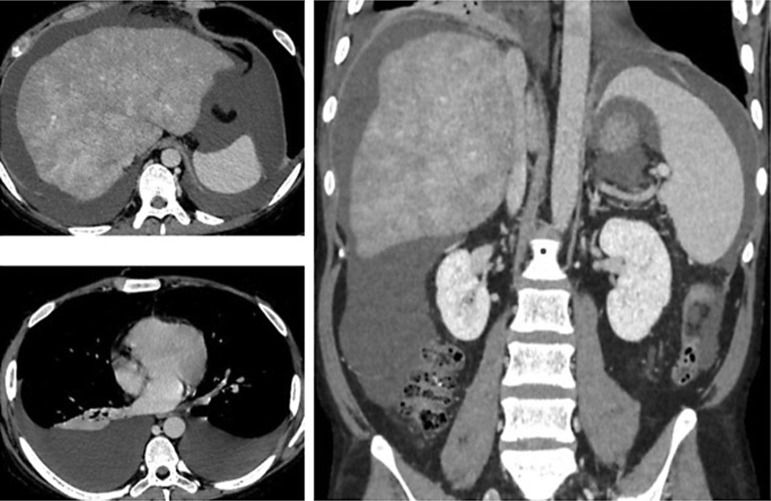

Case presentation: The patient displayed a ruddy complexion, deepening pigmentation in the limbs and abdomen, visible reticular skin pattern changes, and pronounced abdominal striae. Diagnostic investigations included a renal biopsy, which confirmed focal segmental glomerulosclerosis, and an abdominal enhanced CT scan, suggesting hepatic sinusoidal obstruction syndrome. Hematological tests revealed elevated white blood cell count (19.73 × 109/L), hemoglobin level (183 g/L), and platelet count (395 × 109/L). Bone marrow morphology indicated proliferation of red blood cells, white blood cells, and platelets, suspicious for myeloproliferative neoplasm. PCR testing confirmed the presence of the JAK2 V617F mutation, leading to a diagnosis of polycythemia vera. The patient was administered a comprehensive treatment regimen consisting of methylprednisolone, telmisartan, rivaroxaban, furosemide, and spironolactone. This therapeutic approach led to a decrease in the patient's weight and 24-h urinary protein, along with a significant reduction in pleural and abdominal effusions.